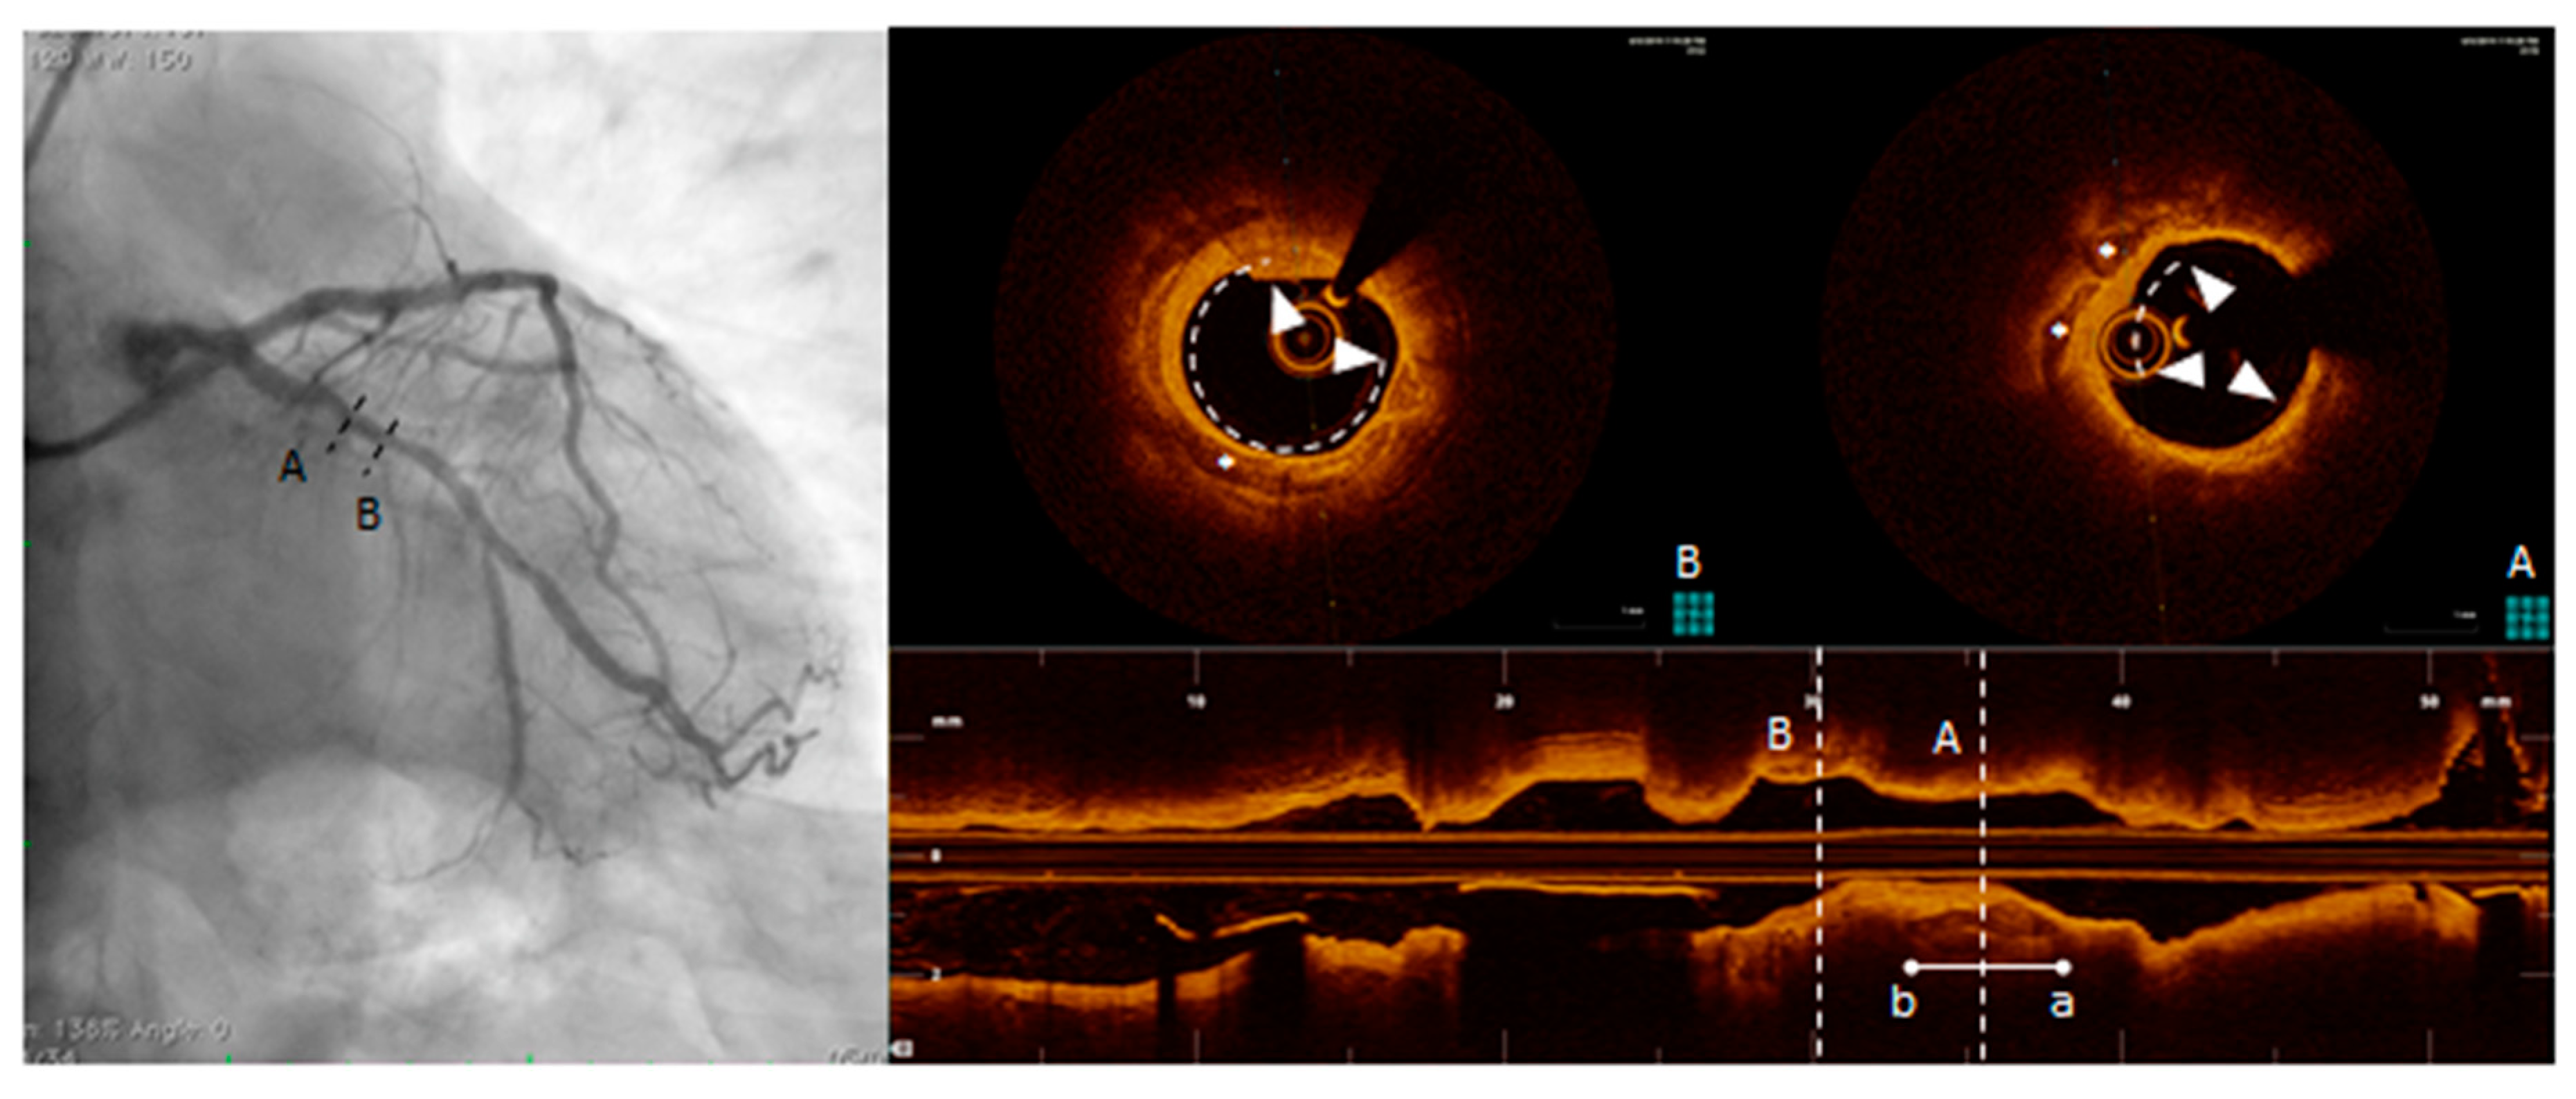

OCT uses a light source in the near-infrared range and measures the time delay of optical echoes reflected by the arterial wall, providing high-resolution cross sectional images of the plaque structure [79,110]. (Figure 6). OCT has about ten times higher axial resolution than IVUS, between 10-20 microns, and lower penetration depth, making this technique most suitable for evaluation of intraluminal structures [111]. Unlike IVUS, penetration of calcification by OCT is greater than for other tissues. Therefore, calcification thickness, area and volume may be quantified [100]. High sensitivity and specificity has been demonstrated for fibrous, fibrocalcific, and lipid-rich plaques [112]. Also, OCT is considered the only imaging modality that can directly measure TCFA and quantify the presence of macrophages and cholesterol crystal in the atherosclerotic plaque [20,104,113,114,115]. OCT imaging of contemporary presence of macrophages and microcalcifications in the same plaque with reciprocal distance smaller than 1 mm (termed co-localization), has been shown to be associated with more vulnerable plaque features [116,117]. These observations seem to indicate that OCT can provide both morphological and disease activity assessment of coronary atherosclerosis. However, the usefulness of OCT is limited by the poor penetration depth (1–2 mm) and attenuation of light transmitted through blood, thrombus and a lipid or necrotic core, all of which prevent the assessment of cross-section plaque and necrotic core area [110].

Figure 6.

Optical coherence tomography (OCT) pull-back on left circumflex. At the proximal part of the vessel, calcific deposits were detected. From distal to proximal, calcification (triangle arrows) surround almost the whole vessel circumference (B, right panel, OCT frame corresponding to the dotted line B, left panel) and more proximally (A, right panel, OCT frame corresponding to the dotted line A, left panel) another spotty, deeper and eccentric calcification.